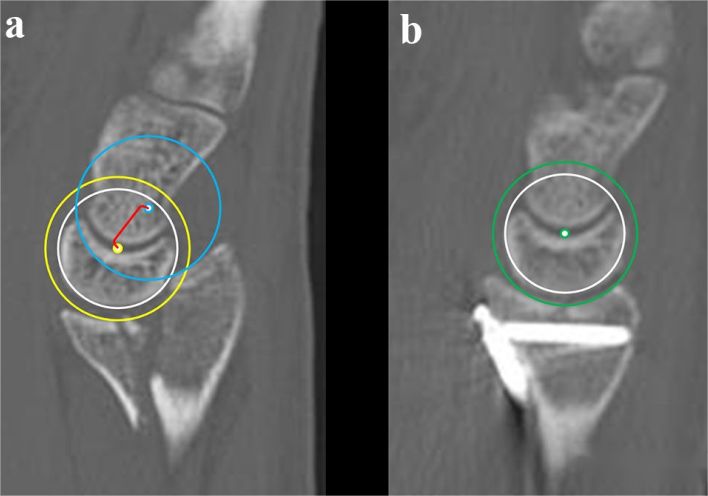

Likewise, in the case of volar Barton’s fracture:

The partially displaced articular surface fragments form Arc 1.

The lunate facet serves as Arc 2.

The dorsal aspect of the radius (normal bone without fracture) represents Arc 3.

Each of these three arcs can be considered as circles. Since the lunate facet and the volar bone fragment are displaced together, Circle 1 (in yellow) shares its center with Circle 2 (in white). ACD represents the distance from this shared center to the center of Circle 3. The surgical objective is to restore ACD to 0, indicating anatomical reduction.